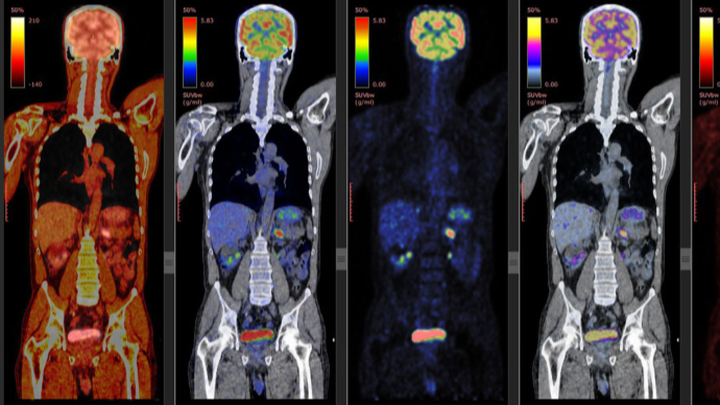

To raise the money needed to get a PET scan.